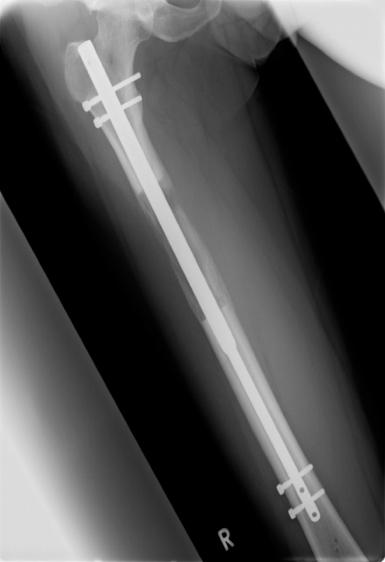

Um die Möglichkeiten der Kallusdistraktion zu nutzen, ohne die Nachteile der externen Fixateure in Kauf nehmen zu müssen, wurden seit den 1980er Jahren voll implantierbare Distraktionsmarknägel entwickelt. Konventionelle Marknägel aus Stahl oder Titan werden

schon seit über 50 Jahren in der Behandlung von Knochenbrüchen verwendet. Auf solchen Marknägeln basieren alle heute auf dem Weltmarkt erhältlichen Distraktionsmarknägel. Diese besitzen ein ausgeklügeltes Innenleben, das ihnen die Distraktion erlaubt.

Fitbone II® im Unterschenkel Albizzia® im Oberschenkel BetzboneÒ im Oberschenkel